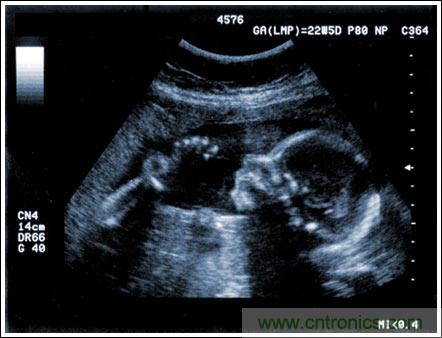

超聲成像系統(tǒng)及主要子功能電子元件的設(shè)計(jì)考慮

【導(dǎo)讀】該應(yīng)用筆記介紹了超聲成像系統(tǒng)的設(shè)計(jì)考慮,討論成像系統(tǒng)的小型化、低成本和便攜化的發(fā)展趨勢,同時闡述了在小型系統(tǒng)中實(shí)現(xiàn)大型車載系統(tǒng)所具備的性能和診斷能力的重要條件。文章探討了超聲系統(tǒng)的子功能以及對電子元件的要求,重點(diǎn)討論了傳感器、高壓復(fù)用器、高壓發(fā)射機(jī)、成像通道接收機(jī)、數(shù)字波束成形、波束成形數(shù)字信號處理及顯示處理等。

通過發(fā)射超聲能量進(jìn)入人體,接收并處理返回的反射信號,相控陣超聲系統(tǒng)可以生成體內(nèi)器官和結(jié)構(gòu)的圖像,映射血液流動和組織運(yùn)動,同時提供高準(zhǔn)確度的血流速度信息。傳統(tǒng)設(shè)計(jì)中,構(gòu)建這樣的成像系統(tǒng)需要大量的高性能相控陣發(fā)射器和接收器,使得車載設(shè)備體積龐大且價格昂貴。近年來,隨著集成工藝的進(jìn)步,設(shè)計(jì)人員能夠獲得小尺寸、低成本而且高度便攜的成像系統(tǒng)方案,并可達(dá)到接近大型成像設(shè)備的性能指標(biāo)。而新的設(shè)計(jì)挑戰(zhàn)依然存在,即在進(jìn)一步提高方案集成度的同時提高系統(tǒng)性能和診斷能力。